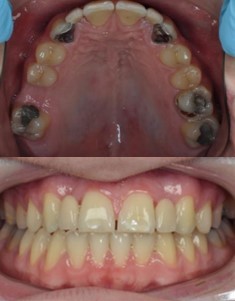

tooth replacement options

2 types of bridgework

adhesive

‘conventional’